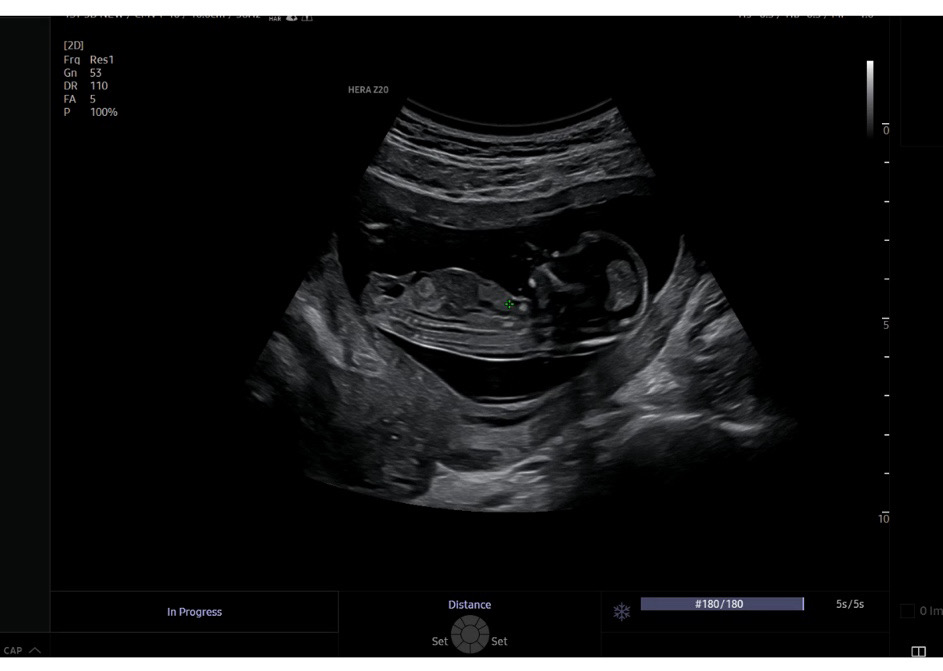

12주 6일차 각도법 궁금해요

12주 6일차 초음파 찍고 왔어요🐥 맘님들이 각도법으로 보시기에는 어떤가요??